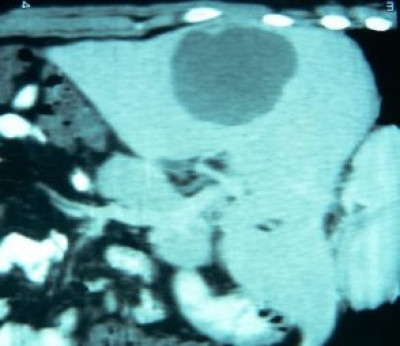

Drenaje percutáneo de absceso hepático

Envíado por Dr. Carlos Miguel Zavaleta Consuegra